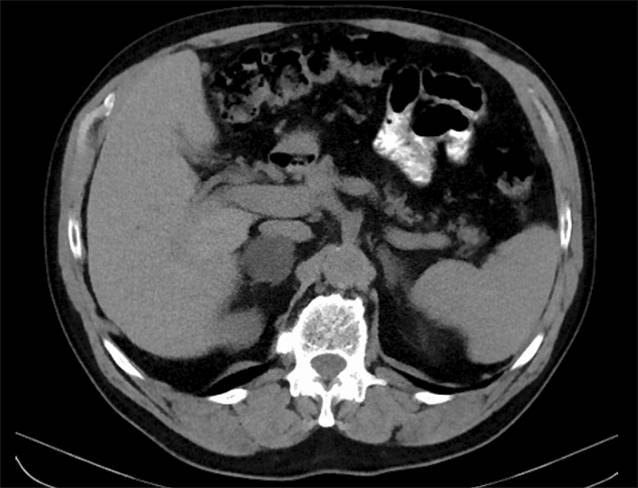

Bildgebung

Abb. 2

Computertomographie eines lokalfortgeschrittenen Nebennierenkarzinoms links mit Peritonealkarzinose (a arterielle KM-Phase, b nativ)